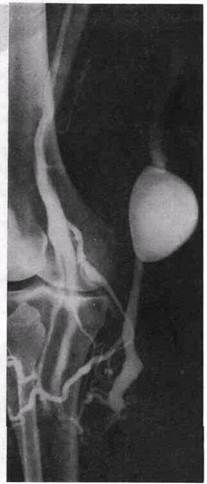

В клинической практике наблюдаются различные варианты, когда встречается относительная недостаточность тех или иных клапанов, что четко определяется при ретроградной флебогра-фии. Во время пробы Вальсальвы при флебоскопии видно, как контрастированная кровь устремляется ретроградно через недостаточные клапаны большой подкожной и бедренной вен или только по одной из названных вен. В случаях недостаточности клапанов глубоких и поверхностных вен контрастное вещество, введенное посредством пункции в бедренную вену при пробе Вальсальвы, распространяется по глубоким и поверхностным венам до средней трети голени. При полноценных клапанах ретроградного распространения контрастного вещества не происходит. При этом четко контрастируется клапан, ограничивающий ретроградный кровоток (рис. 24, а, б).

Рис. 24. Флебограммы нормально функционирующих клапанов глубоких вен бедра (а) и голени (б)—ретроградное контрастировать.